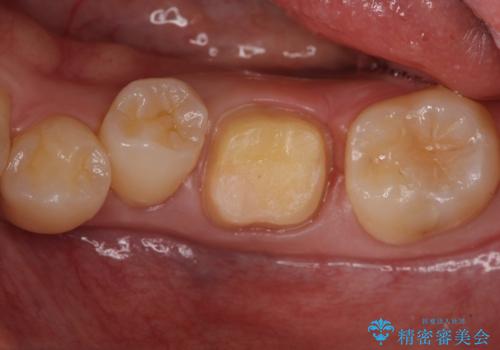

- 左下に詰めた樹脂の変色を主訴に来院されました。

同じ樹脂の材料で詰め直しをしたところでまた変色してしまうリスクが高いため、セラミックでの治療となりました。

- 左下6 仮歯+セラミッククラウン 11000円+110000円費用は治療当時の料金となります